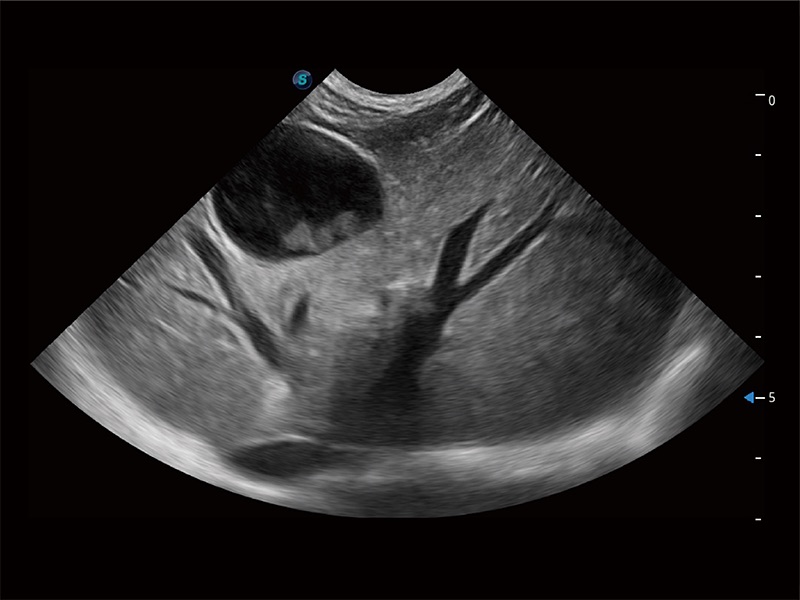

ProPet 80 配备了丰富的心脏探头群、先进的成像技术和专业的心脏测量工具,可帮助动物医生为不同体型和生理结构的动物提供心脏和心肌功能的全面评估。

ProPet 80 专为动物医生设计,对不同的动物体型和生理结构作出了针对性的优化。通过动物影像专用软件,可满足个性化的应用需求,帮助动物医生获得更精确的诊断数据。

为精细结构及组织边缘提供高清晰度的图像和更大的成像视野。帮助减轻医生的用眼疲劳,快速精准获得测量的数据。